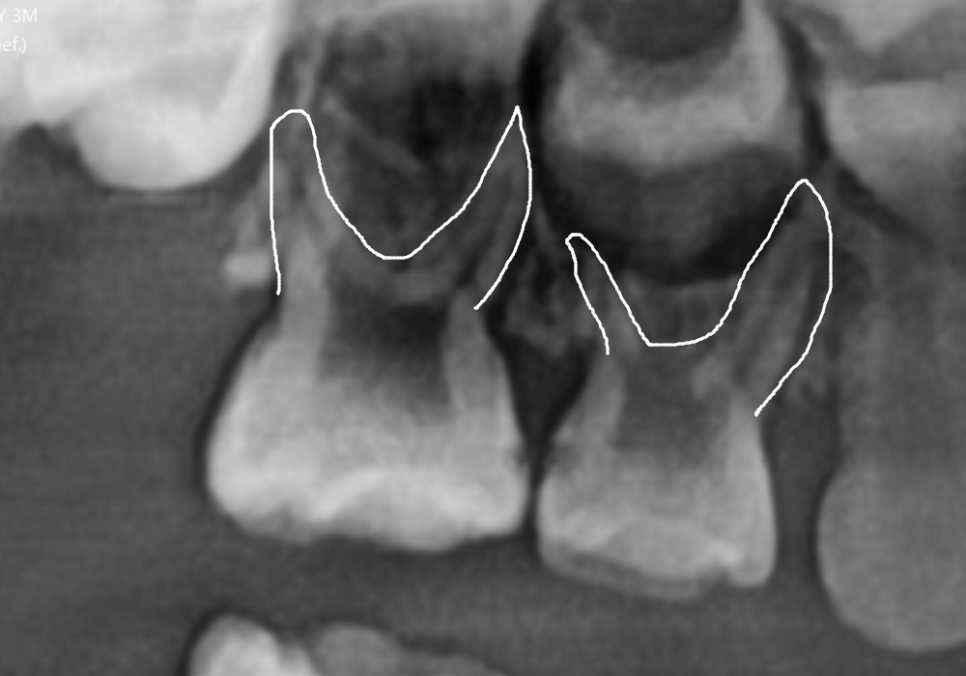

더 큰 문제는 3D CT 상에서

뿌리 끝에 염증이 발견되었다는 점인데요.

뿌리 끝에 이미 염증이 생겨 있었고,

그 염증 때문에 주변 잇몸뼈가 녹아내려

뿌리 끝자락만 간신히 뼈에 걸쳐져 있는 상태였어요.